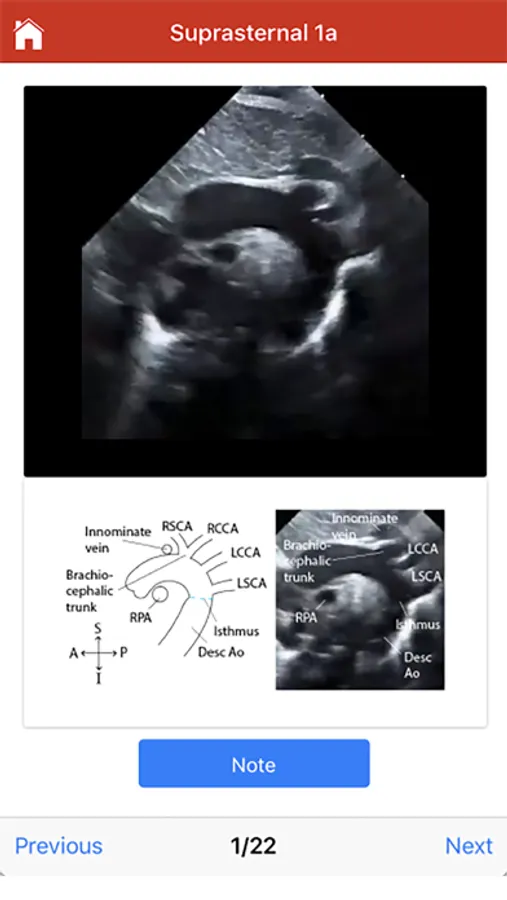

The Echo app provides step-by-step instructions for performing a normal pediatric echocardiogram and uses video clips, images and illustrations to aid in instruction. The app is intended to be used by sonographers at all levels of training, pediatric cardiology fellows, as a teaching aid for pediatric cardiologists and by anyone interested in learning how to perform the normal pediatric echo exam.

The exact images and the order in which the images and views are obtained varies by institution. Each protocol (subcostal, parasternal, apical or suprasternal) can be followed in order by clicking on the next tab at the bottom of the page or you can click on an individual numbered view within the protocol list to be taken directly to that view. The name of the view and instructions will pop-up automatically at the bottom of the page. The instructions and additional notes can also be found in the “NOTE” button at the bottom of the page.